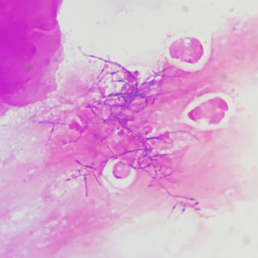

微生物实验室老师结合涂片及菌落形态,怀疑为诺卡菌,立即找到原始标本进行涂片革兰染色以及弱抗酸染色,涂片革兰染色镜检见大量“长丝状有直角分枝”的革兰阳性菌,见图3;弱抗酸染色见弱抗酸阳性菌,见图4。初步判断为诺卡菌。

图3脓液涂片革兰染色(1000×)